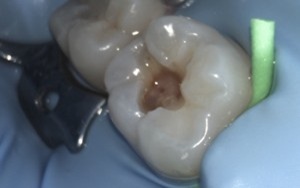

These pictures are a case example of a cosmetic tooth-coloured filling done here at Cornerstone Dental.

Step 3